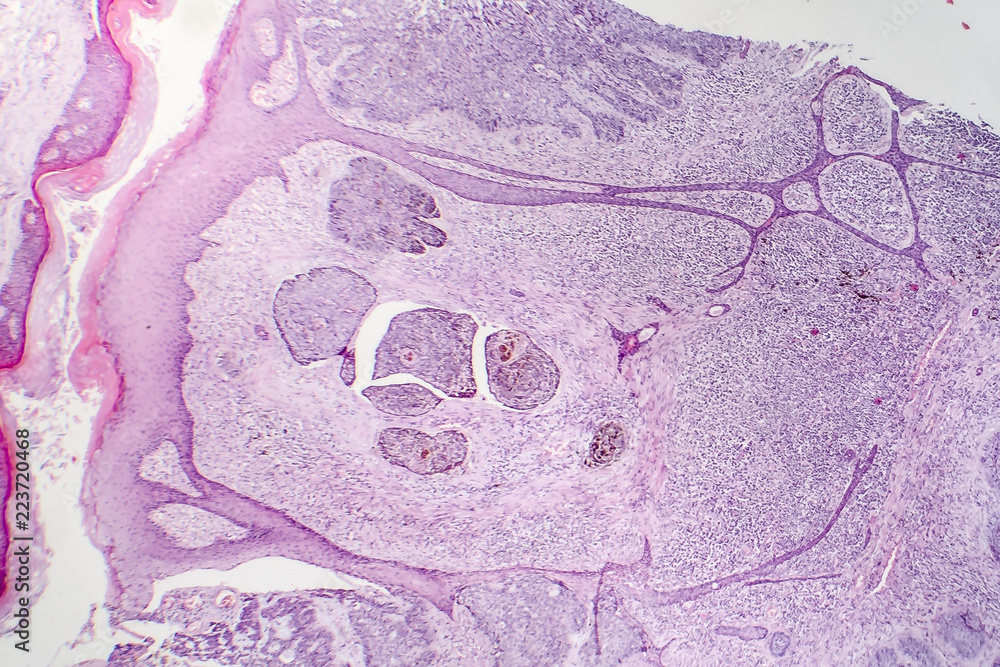

Basal Cell Carcinoma Under Microscope . It is the most common form of skin cancer. Bcc is also known as. Your gp might be able to remove your non melanoma skin cancer in their gp surgery. Basal cell carcinoma (bcc), also known as a rodent ulcer, is the most common form of skin cancer and generally grows very slowly. The typical bcc is a pearly pink or flesh colored papule with telangiectasia. The subtypes have different appearances to the unaided eye, too. The procedure involves excision of the affected skin and examination of the skin removed under the microscope straight away to see if all of the. Basal cell carcinoma (bcc) is a common, locally invasive, keratinocyte cancer (also known as nonmelanoma cancer). These subtypes are based on how tissue samples look under the microscope. They can do this if they have specialist training. Up to 40% of tumors are a. As the most common human cancer worldwide and continuing to increase in incidence, basal cell carcinoma is associated with significant morbidity and cost.

Premium Photo Microscopic view of basal cell carcinoma is a type of Basal Cell Carcinoma Under Microscope As the most common human cancer worldwide and continuing to increase in incidence, basal cell carcinoma is associated with significant morbidity and cost. The typical bcc is a pearly pink or flesh colored papule with telangiectasia. These subtypes are based on how tissue samples look under the microscope. Basal cell carcinoma (bcc) is a common, locally invasive, keratinocyte cancer (also. Basal Cell Carcinoma Under Microscope.

Basal cell carcinoma, skin cancer, light micrograph, photo under Basal Cell Carcinoma Under Microscope These subtypes are based on how tissue samples look under the microscope. Bcc is also known as. Basal cell carcinoma (bcc), also known as a rodent ulcer, is the most common form of skin cancer and generally grows very slowly. The subtypes have different appearances to the unaided eye, too. It is the most common form of skin cancer. They. Basal Cell Carcinoma Under Microscope.